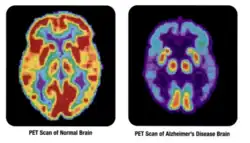

- 2D: Сцинтиграфия (от лат. «знать») — это использование внутренних радионуклидов для создания двухмерных изображений.

Сканирование костей всего тела с помощью ядерной медицины. Сканирование костей всего тела в ядерной медицине обычно используется для оценки различных патологий, связанных с костями, таких как боли в костях, стрессовые переломы, доброкачественные поражения костей, инфекции костей или распространение рака на кость.

Сканирование перфузии миокарда с помощью ядерной медицины с таллием-201 для изображений покоя (нижние ряды) и Tc-Sestamibi для изображений стресса (верхние ряды). Сканирование перфузии миокарда с помощью ядерной медицины играет ключевую роль в неинвазивной оценке ишемической болезни сердца. Исследование не только идентифицирует пациентов с ишемической болезнью сердца; он также предоставляет общую прогностическую информацию или общий риск неблагоприятных сердечных событий для пациента.

Сканирование паращитовидной железы с помощью ядерной медицины демонстрирует аденому паращитовидной железы, прилегающую к левому нижнему полюсу щитовидной железы. Вышеупомянутое исследование было выполнено с одновременной визуализацией технеция-сестамиби (1-я колонка) и йодом-123 (2-я колонка) и методом вычитания (3-я колонка).

Нормальное сканирование гепатобилиарной системы (сканирование HIDA). Сканирование гепатобилиарной системы ядерной медицины клинически полезно для выявления заболеваний желчного пузыря.

Нормальная лёгочная вентиляция и перфузия (V/Q). V/Q-сканирование в ядерной медицине полезно при оценке лёгочной эмболии.

Сканирование щитовидной железы с йодом-123 для оценки гипертиреоза.